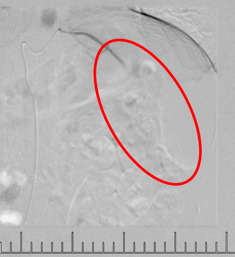

灌注藥物及栓塞后“烏云”消失

肋間動(dòng)脈阻斷營(yíng)養(yǎng)來源